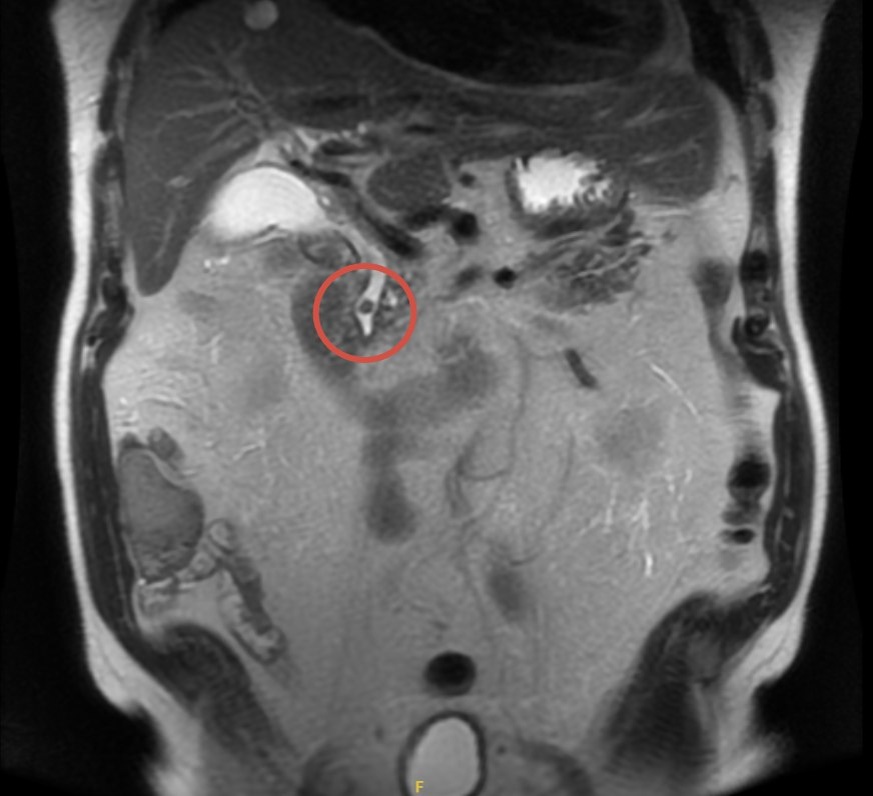

🧲 МРХПГ

✔️ Конкремент до 7 мм в интрапанкреатическом отделе холедоха

✔️ Минимальное расширение общего желчного протока (10–11 мм)

✔️ Желчный пузырь без камней